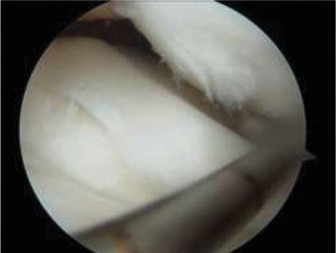

Figure 10–31

Discussion

The correct answer is (C). The arthroscopic images demonstrate a complete discoid meniscus which is covering the entire lateral tibial plateau. As the patient is symptomatic from the meniscus, saucerization is the first step in management. The meniscus is trimmed back using a combination of shavers and biters to a stable peripheral rim, which replicates the width of the native meniscus. Complete meniscectomy would not be indicated in a patient of this age due to the high risk of early onset degenerative arthritis. In fact, even prior to intervention, many discoid menisci have been associated with the development of lateral hemijoint osteochondral lesions. Although chondroplasty may be necessary, the meniscus is the underlying problem causing chondral wear and must be dealt with first. After saucerization is performed, the meniscus is probed and the following arthroscopic image is seen (Fig. 10–33). The next step in management is: